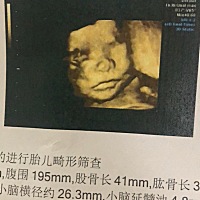

希望我的宝宝一切顺利